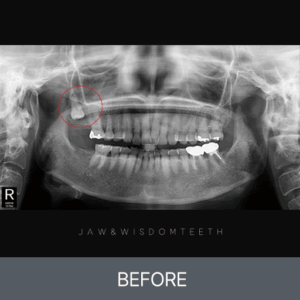

사랑니 CASE